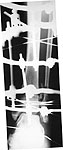

To give the follow up on this patient: A repeat X-ray showed the talus subluxating laterally. A dynamic inversion and eversion strain view pictures showed the lower tibio-fibular syndesmosis opening out. The frame was re-adjusted. Fracture site compressed and valgus corrected. A syndesmotic compression was achieved by adding a washer to the olive and pulling the comminuted lateral malleolus medially. another olive with washer given through talus lateromedially. The equinus that you may see has been corrected. Pictures attached. would welcome critical comments.